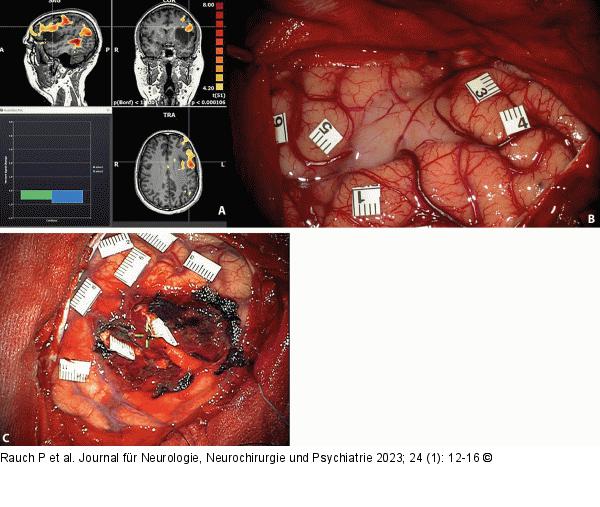

Abbildung 4A-C: Intraoperative Stimulation Präoperatives fMRT eines links operkulären dLGG. A: Bold-Aktivierungen zeigen im Rahmen von Benennungen signifikante Aktivierungen peritumoral. B: Markierung nach intraoperativer elektrischer Stimulation und ausgelösten Paraphasien bzw. Speech- Arrest. Die oberflächliche graue Kortexveränderung macht die Unterscheidung zwischen gesundem und tumorinfiltriertem Gewebe eindeutig. Zahlenmarkierungen werden durch DES intraoperativ eindeutig einem neuropsychologischen Defizit zugeordnet. C: Postoperative Darstellung nach funktioneller Resektion. Markierungen entsprechen kortikalen bzw. subkortikalen DES-Auffälligkeiten. |

Abbildung 4A-C: Intraoperative Stimulation